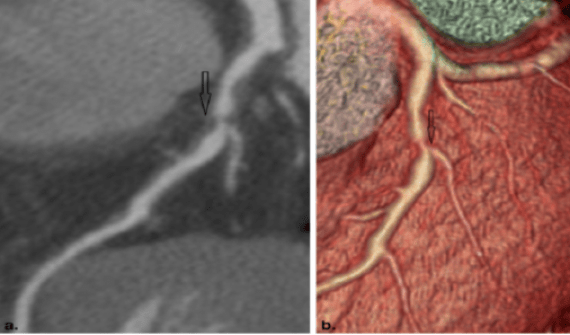

医生靠什么评估冠心病:1.心电图:大部分冠心病病人 , 没有症状发作时的心电图都是基本正常 。 所以 , 心电图正常不能排除冠心病 。 当出现心绞痛症状时 , 发生暂时的T波倒置 , 或ST段下移 。 心电图运动试验更加准确 , 通过运动增加心脏负担 , 在负荷的情况下观察会不会出现上述心肌缺血的心电图表现 。 2.影像学检查:包括心脏超声 , 冠状动脉CT血管成像 , 心脏核磁共振(MRI) , 核医学心肌灌注检查等 。 各种影像学检查各有优势 , 医生会根据您的病情选择合适的检查方法 , 目前应用比较广泛的是心脏超声和冠状动脉CT血管成像检查 , 特别是冠状动脉CT血管成像检查 , 可以直接观察到冠状动脉内是否存在斑块及血管狭窄 , 提供诊断冠心病的直接证据 。 当然 , 目前诊断冠心病的金标准还是经导管的冠状动脉造影检查 , 该检查属于有创检查 , 必须住院在医院导管室内完成 , 存在一定的风险性 。 可喜的是 , 上述冠状动脉CT血管成像等无创的影像学检查可以在门诊完成 , 且可以明确是否存在冠心病 。 故当您怀疑到自己存在冠心病时 , 一定不要讳疾忌医 , 及时就诊 , 让医生判断病情 , 早诊早治 , 以免延误病情 。

冠状动脉CT血管成像示冠状动脉斑块形成 , 导致冠状动脉管腔狭窄 , 明确诊断冠心病